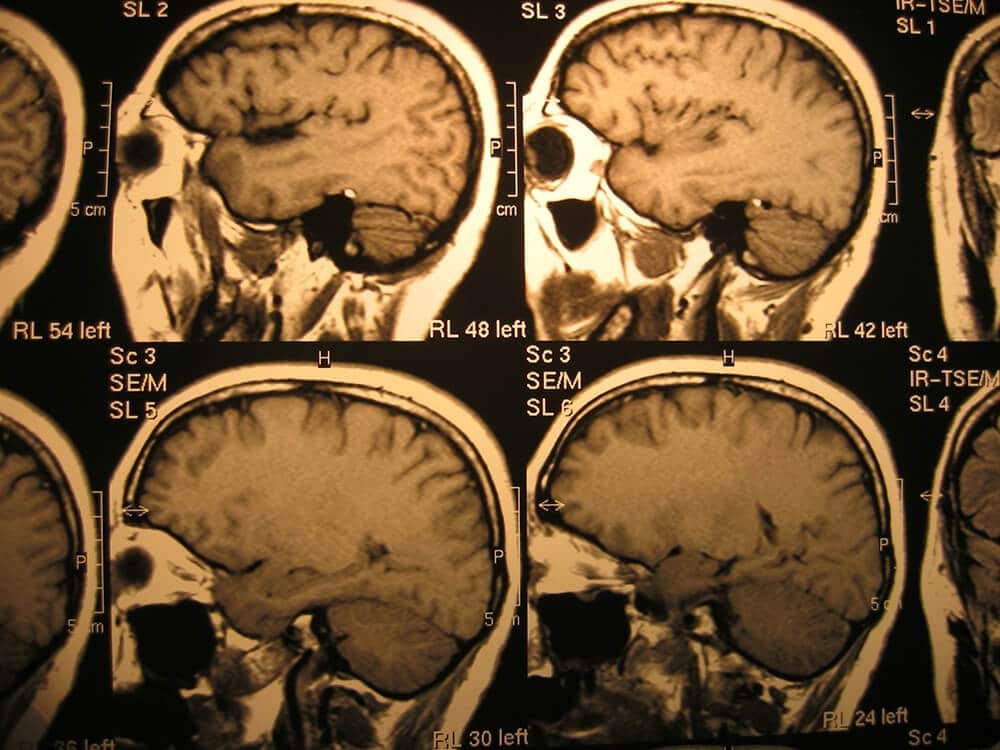

A brain injury can completely change your life. You may have to adjust to a new normal—which means you may not be able to return to your job or participate in activities and hobbies you did before the injury. Many traumatic brain injuries (TBIs) are also life-threatening. Why is this? Let’s take a look at how serious injuries to the brain can be.

A traumatic brain injury occurs when an external force impacts the brain and the brain’s functions are affected. The head can suffer a blow or bump or a foreign object can go through the skull and injure the brain. These severe injuries can likely cause permanent health problems or death.

These injuries are life-threatening because they’re affecting a major organ and often need immediate and speedy medical attention. If you’ve suffered from a TBI, it may be because of someone else’s negligence.